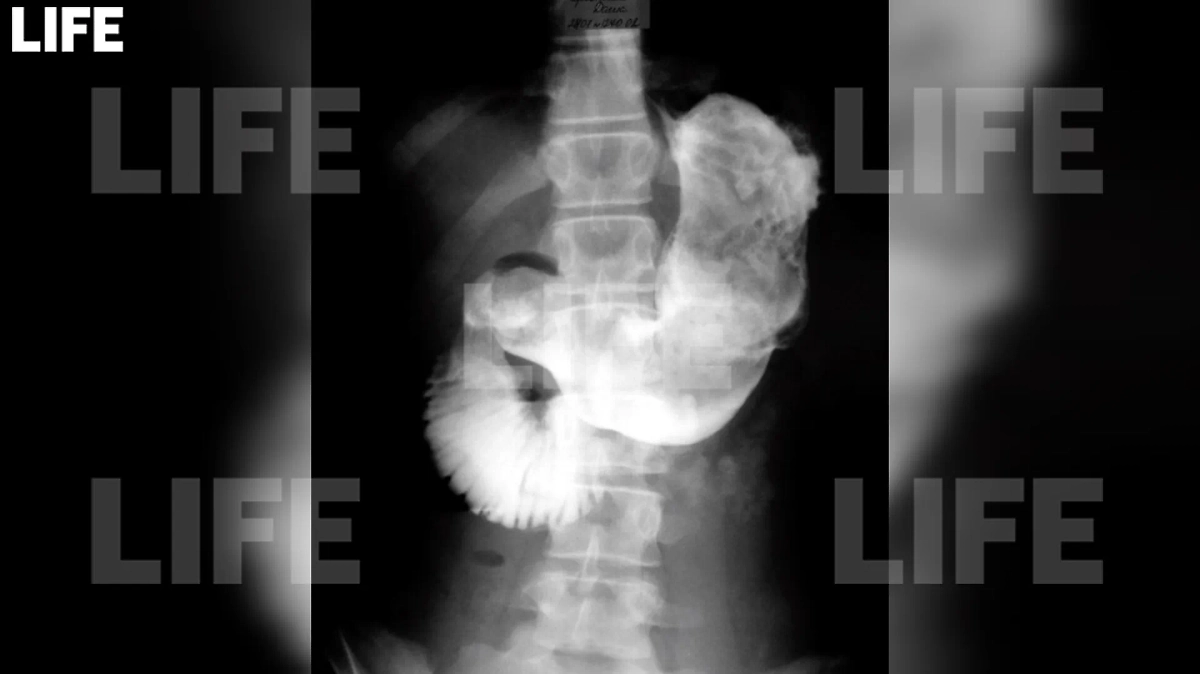

Ком волос, который достали из желудка 14-летней девочки в Москве, на снимке. Фото © Предоставлено Life

Врачи Детской городской клинической больницы имени З.А. Башляевой в Москве удалили из желудка 14-летней девочки трихобезоар — это спутанные волосы, смешанные с остатками пищи и желудочной слизью. Длина обнаруженного инородного тела достигала 40 сантиметров, а ширина — 12.

Как рассказали Life.ru в столичном Депздраве, всё началось с жалоб подростка на боль в животе. Причём других симптомов у неё не было, рвоты не наблюдалось. Во время ультразвукового исследования (УЗИ) брюшной полости в просвете желудка и двенадцатиперстной кишки было обнаружено объёмное образование. Компьютерная томография (КТ) также подтвердила наличие инородного тела. Врачи пришли к выводу, что перед ними огромный ком волос. На следующий день девочку прооперировали.

По его словам, юной пациентке необходимо было провести операцию из-за кишечной непроходимости. Трихобезоар заблокировал не только желудок, но и двенадцатиперстную кишку. Хирурги успешно удалили образование, полностью восстановив функции желудочно-кишечного тракта (ЖКТ) девочки. Пациентку уже выписали домой.